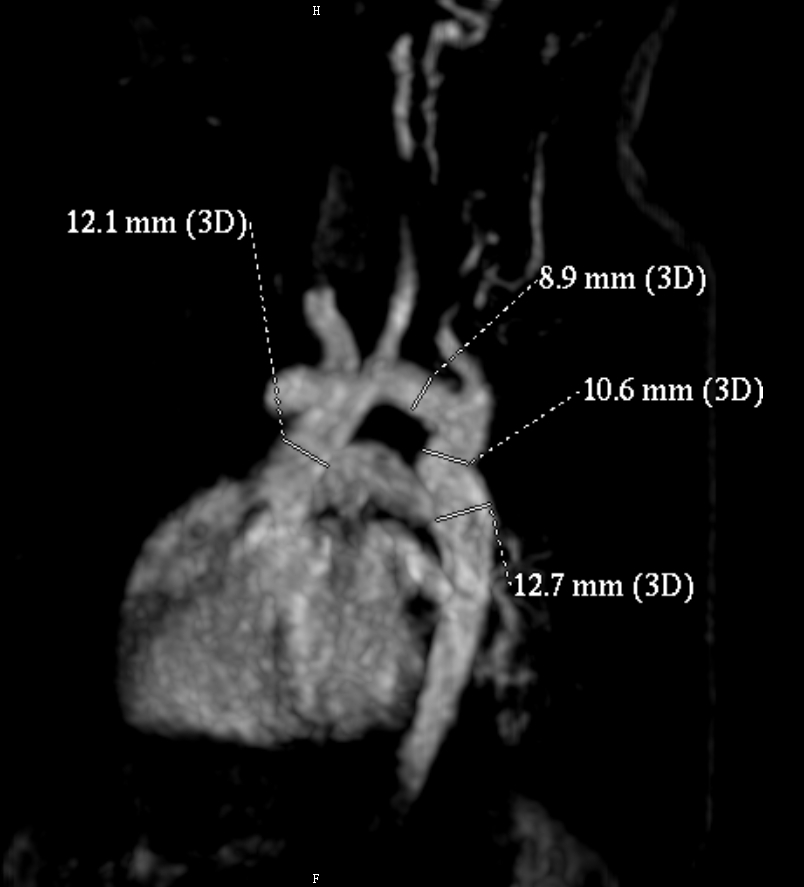

心室大动脉连接一致,左弓,未见明显动脉导管未闭,主动脉弓降部扭曲,此处直径10.6mm,最大流速1.44m/s,平均流速0.52m/s,远端降主动脉12.7mm,升主动脉直径12.1mm,弓部直径8.9mm,肺动脉总干及左右肺动脉发育可。

9 c) a* [: f( I放射学诊断:主动脉弓降部扭曲,请结合临床,建议随访

血管稍有扭曲,但直径尚可,室缺应该也没有问题。

图像 1.jpg